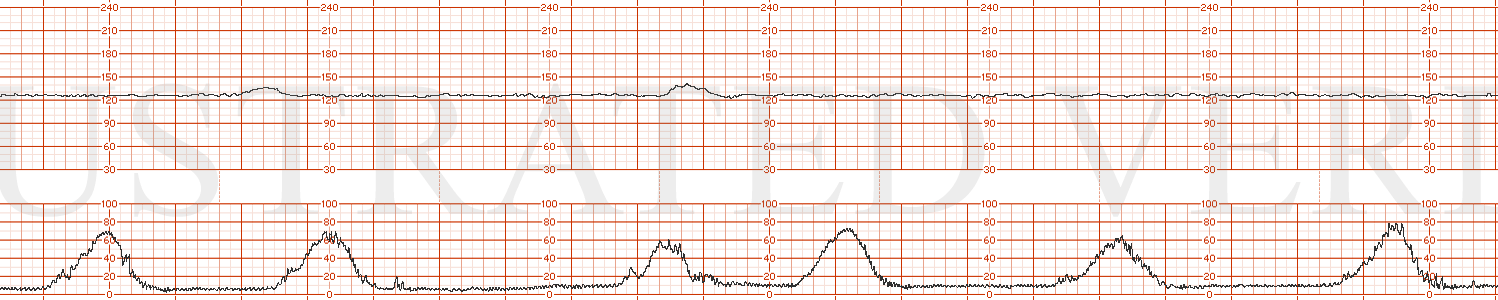

STRIP 50

1. Ctxs – 8 contractions – as above strip 2

Baseline 155 bpm with min-mod variability varying 4-6 bpm transitioning every 6 minutes or so from 4 to 6 to 4 bpm

Decels – Variable decelerations at CTX 2, 4, 6, 8, - of 30 sec, 40 sec, 35 sec and 50 sec with nadir to 130, 135, 120, 115 nadir at that level for 15 sec each.

Accels – none; no scalp stim done